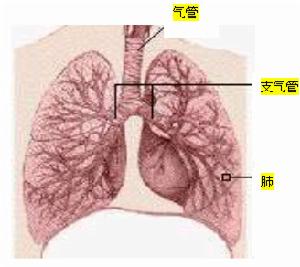

肺炎是指終末氣道、肺泡和肺間質的炎症,可由病原微生物、理化因素、免疫損傷和藥物所致。老年肺炎指的是65歲以上老年人所患肺炎。不論開發中國家還是已開發國家,肺炎均是導致老年人死亡的主要原因之一。隨著我國人口老齡化的發展,老年肺炎的發病率正在逐年增加,應引起我們的高度重視。疾病概述

解剖結構和肺功能變化:鼻腔黏膜和支氣管黏膜的萎縮,支氣管軟骨鈣化或骨化、纖毛運動減弱,終末細支氣管上皮細胞進行性改變,支氣管腺體增生,肺泡管擴張、肺泡擴大、破裂,肺泡毛細血管變窄或斷裂、肺泡毛細血管床減少,肺彈性回縮力下降。上述解剖結構和肺功能的變化可引起呼吸道的保護性反射減弱,使得病原體極容易進入老年人的下呼吸道。免疫功能下降:老年人外周血T淋巴細胞數僅為青年人的70%-75%、且其發生功能異常,B淋巴細胞分泌特異性抗體能力下降,呼吸道分泌IgA下降,病原菌更容易侵入呼吸道黏膜,中性粒細胞趨化能力下降、粘附能力增高,補體活性、血漿纖維蛋白結合素含量下降。